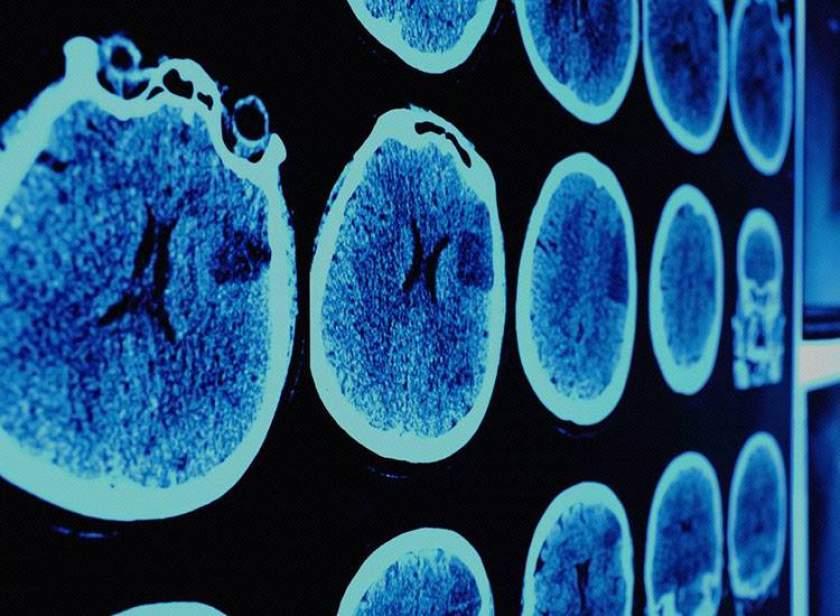

Oamenii de ştiinţă de la Universitatea Stanford ar fi găsit leacul pentru cancer! Dr. Nicolae Bacalbaşa: "Există Dumnezeu!"

Oamenii de ştiinţă de la Universitatea Stanford ar fi găsit leacul pentru cancer